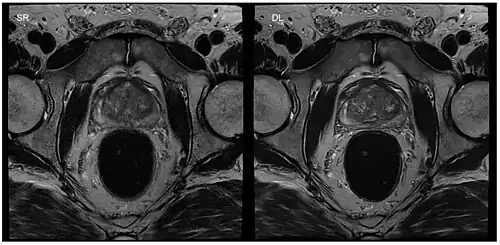

Standard reconstruction (left) versus reconstruction with DL (right) for a T2-weighted turbo spin-echo scan of the prostate

Machine learning

Image reconstruction in RT-MRI benefits from machine learning (ML) or deep learning (DL). A nonlinear kernel, or mapping function, can be developed from the ACS to fill in k-space data and generate the final image.[37] This process as a whole significantly accelerates the MRI process. Image segmentation or identification of lesions can be achieved through machine learning. In deep learning, with a convolutional neural network, the mapping function can be specified by the network. ML and DL improve image resolution as well as imaging speed.[37]